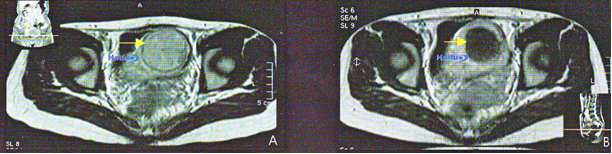

8. Компьютерная томография у 20-летнего пациента, леченного с помощью HIFU по поводу остеосаркомы дистальной трети бедра.

На А1, 2 изображениях до сеанса HIFU в мягких тканях бедра визуализируется опухоль (стрелка), определяется разрушение кортикального слоя кости опухолевой тканью (стрелка). В1 и 2 изображения получены через 5 лет после HIFU. Определяется исчезновение опухоли мягких тканей и восстановление кортикального слоя кости (стрелка).